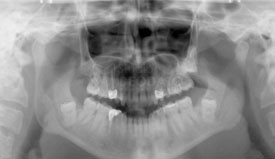

Estrazione elementi dentari inclusi/disodontiasi

Non sempre la chirurgia orale , preposta alla estrazione del terzo molare(o dente del giudizio) è tecnicamente di facile esecuzione e puo' essere praticata in un convenzionale ambuatorio odontoiatrico perchè la difficoltà di estrazione chirurgica è in rapporto sia alla posizione del dente ritenuto nell'osso ma anche in rapporto alla vicinanza con il canale contenente il nervo mandibolare.

Nei nostri nosocomi viene attentamente valutato caso per caso e dopo attento e scrupoloso approfondimento diagnostico (OPT - TC - TC Cone Beam), a seconda della complessità estrattiva , organizzata la seduta operatoria che puo' essere eseguita ambulatorialmente in regime di day surgery(il paziente viene ricoverato al mattino e dimesso il giorno stesso) o nei casi piu' complessi in sala operatoria con anestesia generale e supporto anestesiologico.